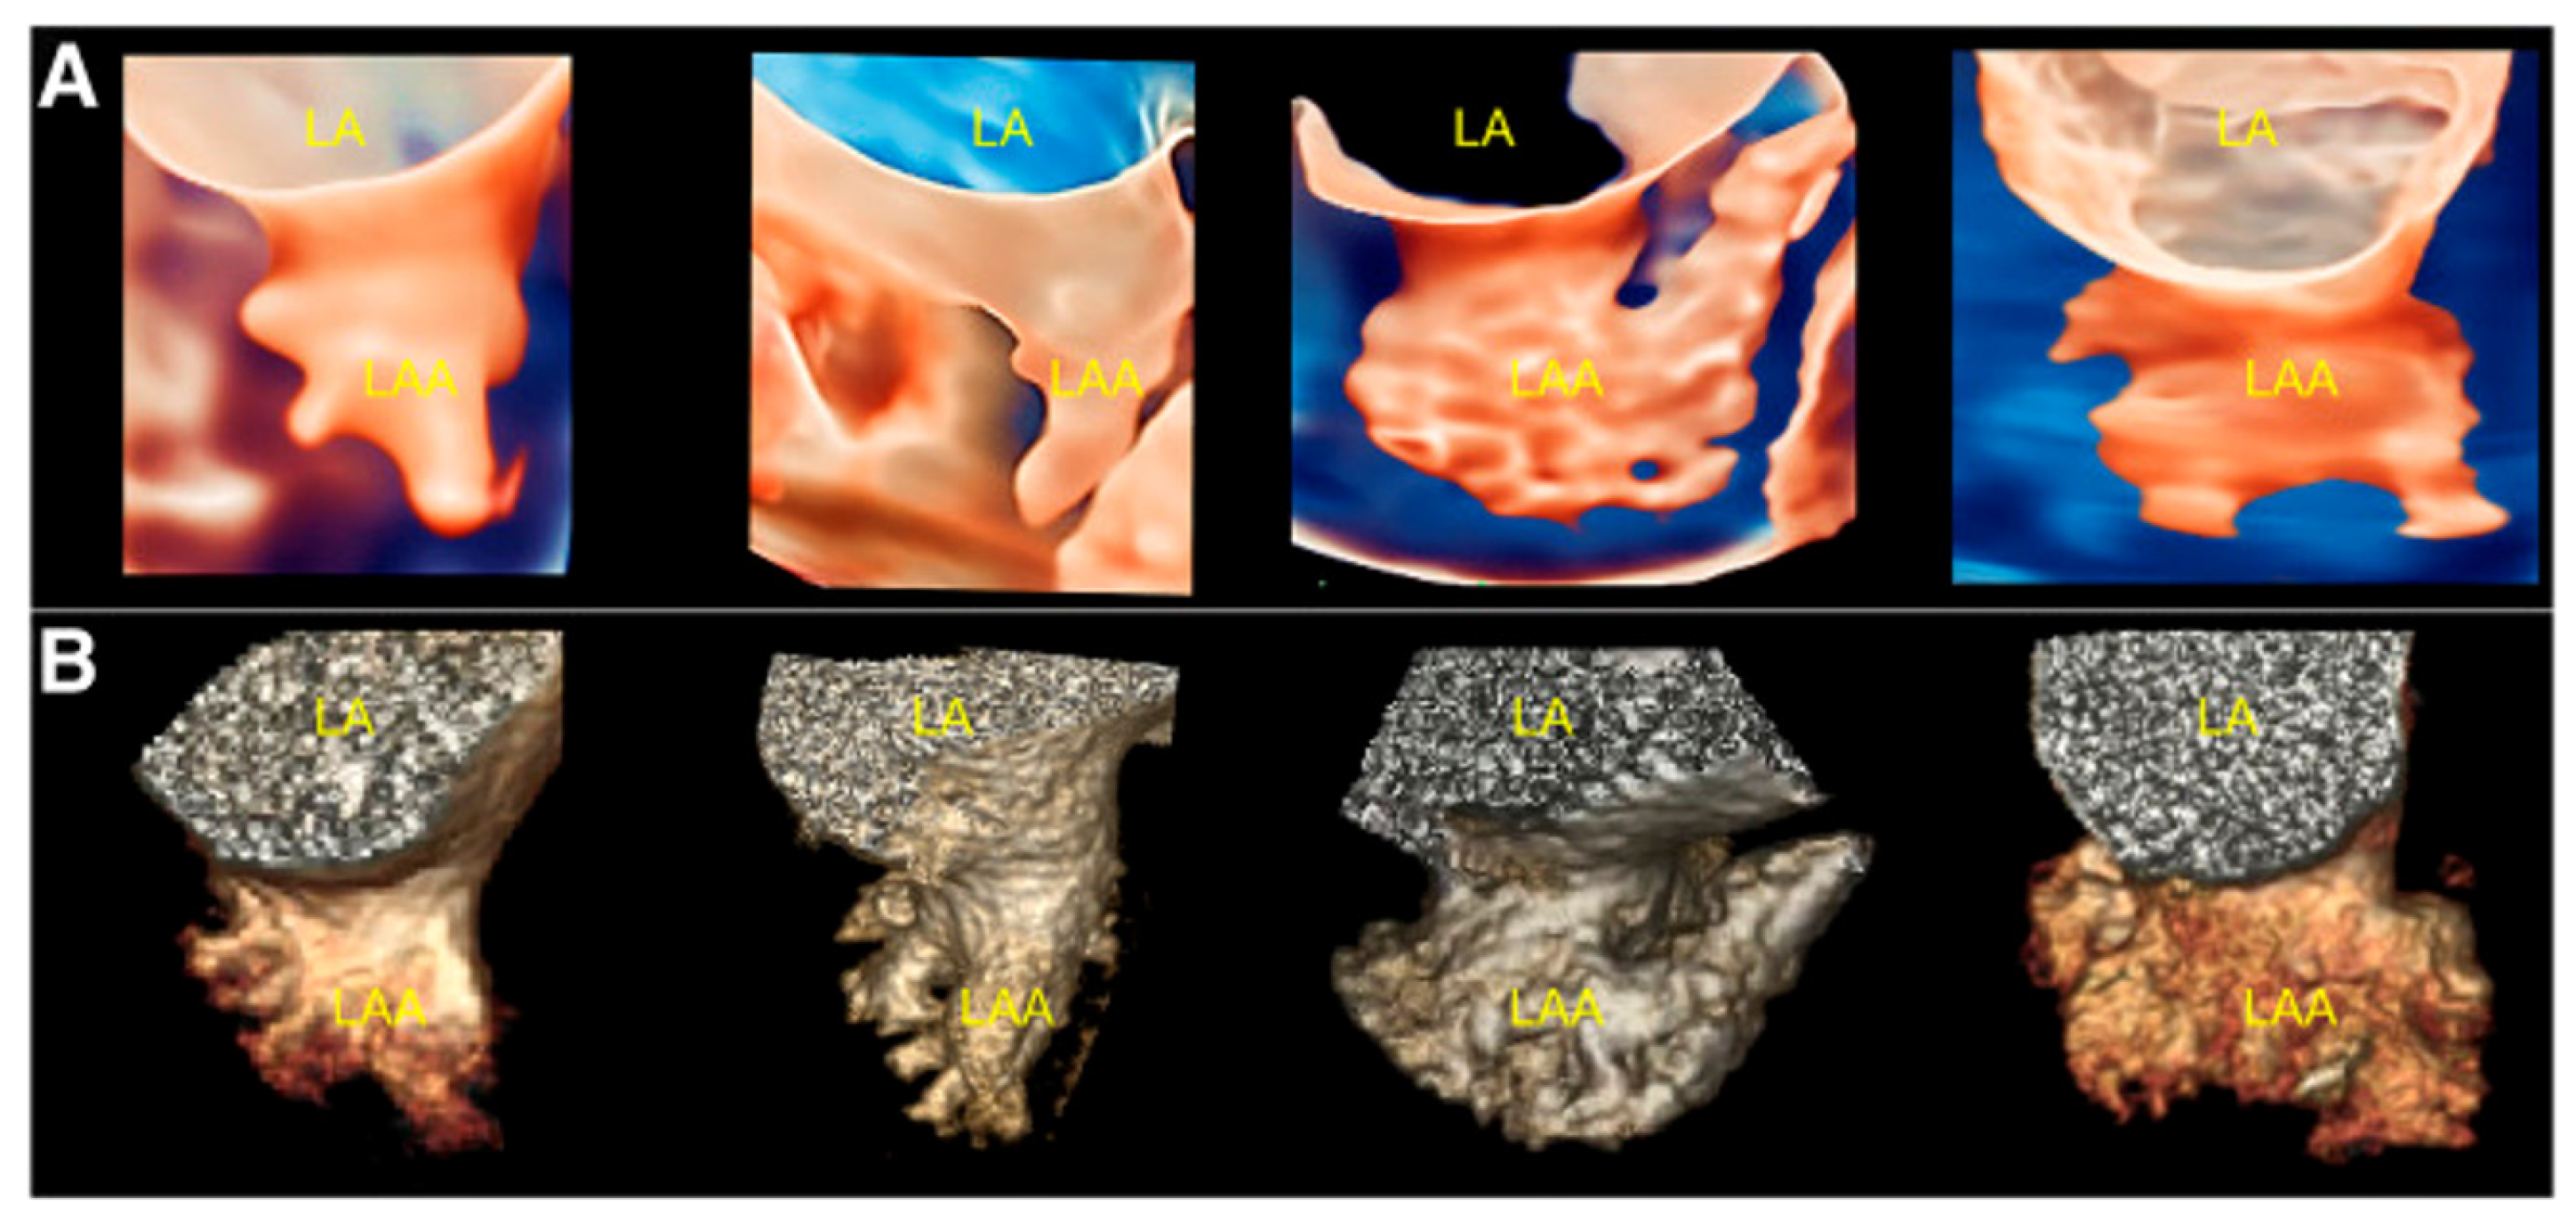

- Sun, A.; Ren, S.; Xiao, Y.; Chen, Y.; Wang, N.; Li, C.; Tan, X.; Pan, Y.; Sun, F.; Ren, W. Real-Time 3D Echocardiographic Transilluminated Imaging Combined with Artificially Intelligent Left Atrial Appendage Measurement for Atrial Fibrillation Interventional Procedures. Front. Physiol. 2022, 13, 1043551. [Google Scholar] [CrossRef]

- Okafor, J.; Rana, B.S. Importance of Echocardiography in Navigating Left Atrial Appendage Function, Thrombus Exclusion and Percutaneous Closure. Clin. Res. Cardiol. 2024, 1–3. [Google Scholar] [CrossRef]

- Nucifora, G.; Faletra, F.F.; Regoli, F.; Pasotti, E.; Pedrazzini, G.; Moccetti, T.; Auricchio, A. Evaluation of the Left Atrial Appendage with Real-Time 3-Dimensional Transesophageal Echocardiography Implications for Catheter-Based Left Atrial Appendage Closure. Circ. Cardiovasc. Imaging 2011, 4, 514–523. [Google Scholar] [CrossRef] [PubMed]

- Vainrib, A.F.; Harb, S.C.; Jaber, W.; Benenstein, R.J.; Aizer, A.; Chinitz, L.A.; Saric, M. Left Atrial Appendage Occlusion/Exclusion: Procedural Image Guidance with Transesophageal Echocardiography. J. Am. Soc. Echocardiogr. 2018, 31, 454–474. [Google Scholar] [CrossRef] [PubMed]